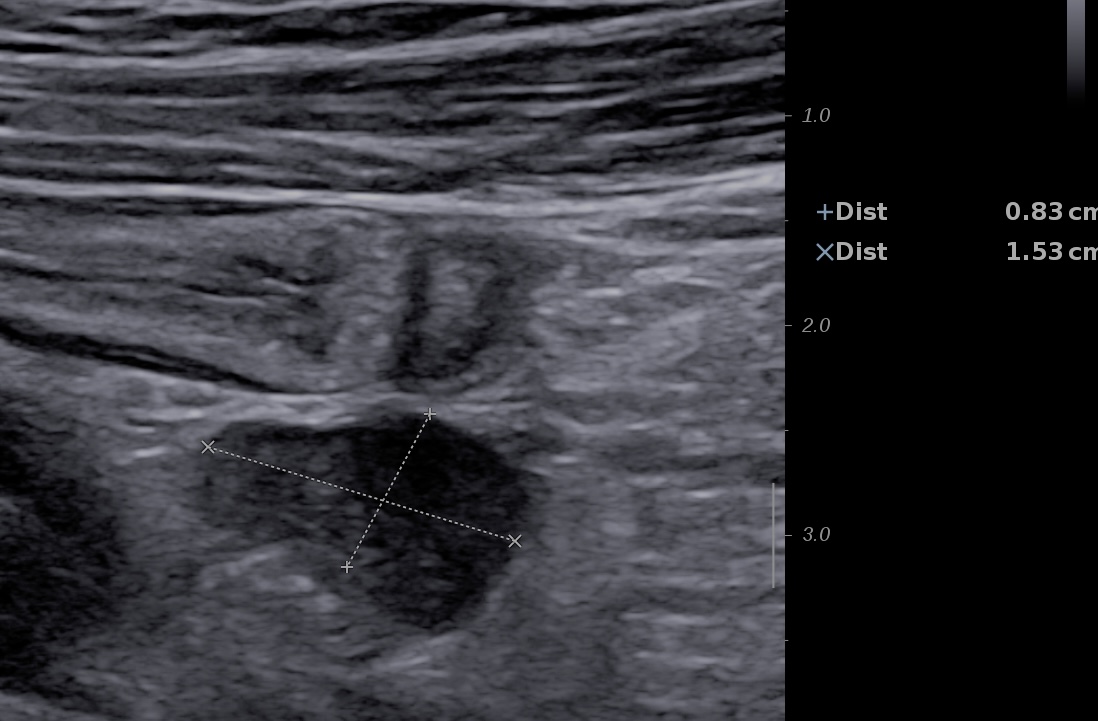

- Classiquement on mesure le petit axe, > 5 mm en cas d'inflammation. C'est surtout vrai pour l'iléon

Ci-dessous ganglions de petite taille (5 mm) arrondis, hypo échogènes et situés au sein d'une inflammation de la graisse